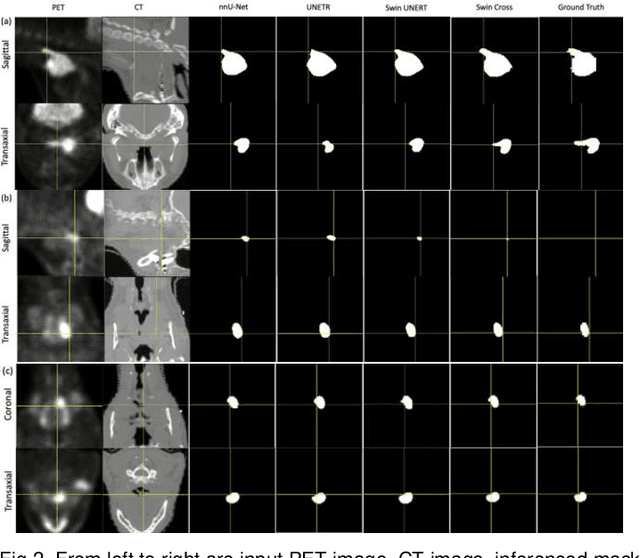

Abstract:Radiotherapy (RT) combined with cetuximab is the standard treatment for patients with inoperable head and neck cancers. Segmentation of head and neck (H&N) tumors is a prerequisite for radiotherapy planning but a time-consuming process. In recent years, deep convolutional neural networks have become the de facto standard for automated image segmentation. However, due to the expensive computational cost associated with enlarging the field of view in DCNNs, their ability to model long-range dependency is still limited, and this can result in sub-optimal segmentation performance for objects with background context spanning over long distances. On the other hand, Transformer models have demonstrated excellent capabilities in capturing such long-range information in several semantic segmentation tasks performed on medical images. Inspired by the recent success of Vision Transformers and advances in multi-modal image analysis, we propose a novel segmentation model, debuted, Cross-Modal Swin Transformer (SwinCross), with cross-modal attention (CMA) module to incorporate cross-modal feature extraction at multiple resolutions.To validate the effectiveness of the proposed method, we performed experiments on the HECKTOR 2021 challenge dataset and compared it with the nnU-Net (the backbone of the top-5 methods in HECKTOR 2021) and other state-of-the-art transformer-based methods such as UNETR, and Swin UNETR. The proposed method is experimentally shown to outperform these comparing methods thanks to the ability of the CMA module to capture better inter-modality complimentary feature representations between PET and CT, for the task of head-and-neck tumor segmentation.